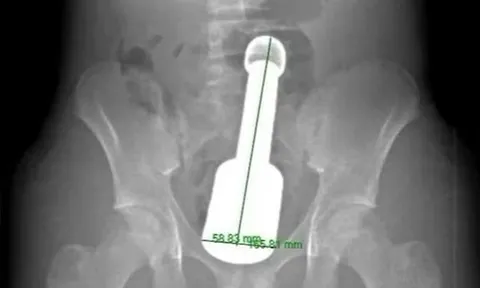

Đau bụng dữ dội nhiều ngày, người đàn ông suýt trả giá đắt, bác sĩ cảnh báo thói quen nhiều người mắc phải

Trước đó, nam bệnh nhân đến khám tại bệnh viện trong tình trạng đau vùng thượng vị và hạ sườn phải, đồng thời có vàng da, vàng mắt, mệt mỏi. Sau khi thăm khám, bác sĩ đã phát hiện nguyên nhân nguy hiểm, suýt nữa phải trả giá bằng cả tính mạng.